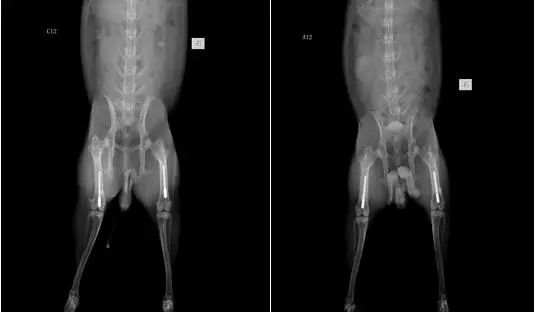

③、股骨植入